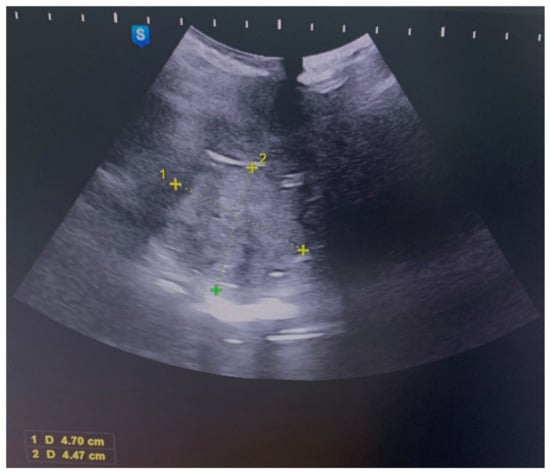

A 21-year-old patient, a virgin without a significant medical history, was addressed to our hospital for abundant vaginal bleeding. The local examination could not be performed due to her virginity. We performed abdominal and perineal ultrasounds, which showed a cervical tumor (Figure 1).

Figure 1. Abdominal ultrasound image of an irregular lesion occupying the vagina of 4.7 cm/4.47 cm.